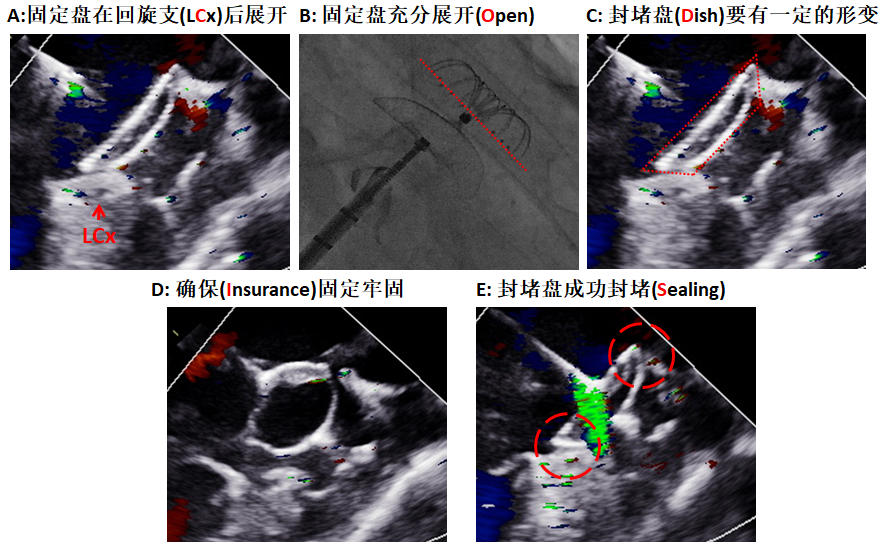

图5 “CODIS”原则评价LEFTEAR封堵器是否封堵成功。A:固定盘在回旋支(LCx)后展开,红色箭头提示TEE下LCx的开口位置; B:固定盘充分展开(Open),固定盘的末端与连接在封堵盘和固定盘之间的显影标志在一条直线(红色虚线);C:封堵盘(Dish)要有一定的相对形变;I:通过牵拉试验确保固定牢固(Insurance); S:封堵盘成功封堵(Sealing),红色虚线提示封堵盘上缘和下缘,均没有残余分流。